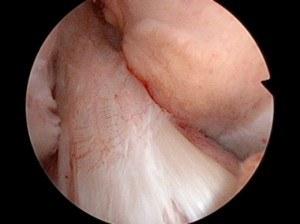

Normal Anterior Cruciate Ligament

Normal meniscus and articular cartilage